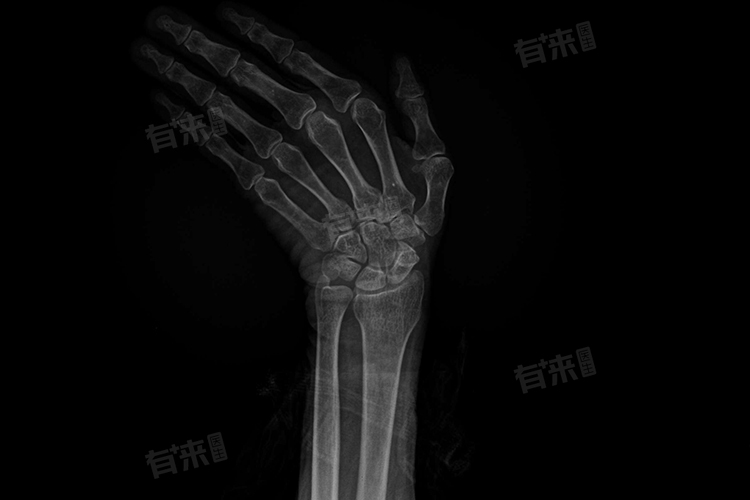

手腕骨头错位一般不能自行修复,因为骨头错位后,周围的软组织也会受到不同程度的损伤,而骨头本身并不具备自行恢复到原来位置的能力,手腕骨头错位后需要及时就医,接受专业的治疗。

- 手腕骨头错位的治疗方法主要取决于错位的程度和软组织损伤的情况,对于轻度的手腕骨头错位,如果没有明显的骨折或韧带撕裂,可以采取保守治疗的方式。包括使用支具或石膏进行固定,以维持手腕的稳定性和防止进一步损伤。此外可以配合冷敷、热敷以及非甾体抗炎药等药物来缓解疼痛和肿胀。在固定期间,患者需要避免使用患肢进行剧烈活动,并遵循医生的指导进行康复锻炼。

- 但对于严重的手腕骨头错位,尤其是伴有骨折或韧带撕裂的情况,通常需要进行手术治疗。手术治疗的目的是通过切开复位和内固定来恢复骨骼的正常位置和结构,并修复受损的软组织。手术后,患者需要在医生的指导下进行康复锻炼,以促进手腕功能的恢复。

如果患者试图自行处理或忽视治疗,可能会导致错位加重、软组织损伤加剧以及手腕功 能障碍等严重后果。因此,一旦出现手腕骨头错位的症状,如疼痛、肿胀、活动受限等,患者应立即就医并接受专业的治疗。通过合理的治疗和康复锻炼,患者可以最大限度地恢复手腕的功能和减少后遗症的发生。